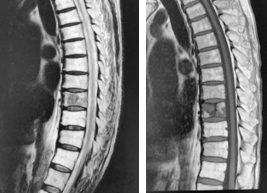

腎癌の胸椎転移に対するTES手術

脊椎腫瘍では脊椎骨が原発腫瘍やがんの転移腫瘍に占拠された結果、骨を破壊し脊柱の支持性がなくなり局所の痛みを生じます。さらに、腫瘍が脊髄や馬尾神経を圧迫して痛みや神経麻痺を引き起こします場合もあります。その他、脊髄や神経根の圧迫の症状として歩行障害、病的反射、腱反射亢進、膀胱直腸障害、肋間神経痛(胸部痛、しびれ)などが生じます。腫瘍が胸椎にあれば背中からのみで手術を行い、腰椎にあれば周囲の組織を安全に避けるために脇腹からの手術も追加します。

胸椎の腫瘍の場合

背中の皮膚を切開します。摘出する椎体の頭尾側にスクリューを設置し、ロッドで接続して脊椎を強固に固定します。後方より、肋骨を切除し、椎体前面、側面を剥離して、脊髄をよけながら、腫瘍に侵された椎体を一塊として摘出し、同部位に金属性のメッシュに局所骨あるいは腸骨を設置します。